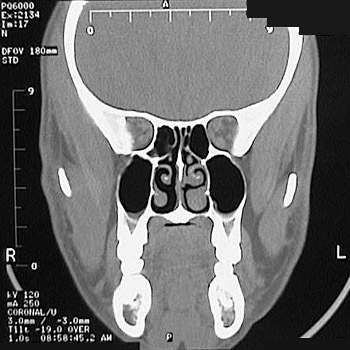

This is a normal sinus CT scan demonstrating the orbit and ethmoid sinus and nasal cavity and concha and maxillary sinus and maxilla and mandible in the anterior skull.